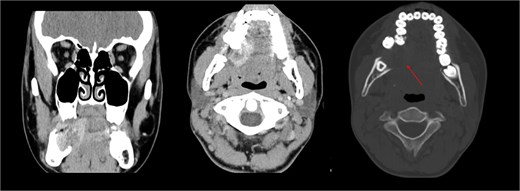

The patient was admitted from the clinic for urgent evaluation. Routine blood investigations were normal. An orthopantomogram revealed displacement of the second and third molars and a poorly defined superior margin of the alveolar process, suggesting osseous involvement (Fig. 2). Contrast-enhanced computed tomography (CT) of the facial bones and neck demonstrated a well-defined lucent lesion within the mandibular body with exophytic soft tissue extension into the oral cavity (Fig. 3). Magnetic resonance imaging (MRI) of the neck illustrated the hyperintense soft-tissue component with no rim enhancement or necrosis (Fig. 4). There was no lymphadenopathy noted clinically or radiograpgically.

CT showing well defined lucent lesion within the body of the right side of the mandible with exophytic soft tissue component extending into oral cavity.